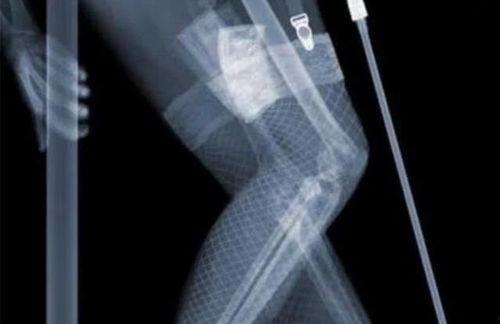

在医疗领域,x光透视频可是大显身手。医生们可以通过它来观察患者的骨骼、内脏等部位,从而做出准确的诊断。比如,骨折、肿瘤等疾病,通过x光透视频就能一目了然。